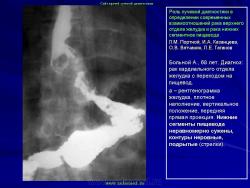

Возможности новых технологий

В арсенале современной лучевой диагностики рака желудка имеются средства, позволяющие внести ясность в случаях, когда возникает расхождение рентгенологического и эндоскопического заключений. Эндоскопия, являясь великолепным методом диагностики, не всегда может ответить на все интересующие клиницистов вопросы, и с учетом неуклонного роста диффузных и смешанных раков ее возможности в выявлении рака желудка все же ограничены. Здесь следует более четко обозначить важную возможность проведения дообследования. Речь идет о так называемых новых технологиях. Лучевая диагностика, обогатившись такими методами, как УЗИ, КТ и МРТ (а это особенно важно при сегодняшней ситуации с раком желудка), может в отдельной клинической ситуации дополнить имеющуюся диагностическую информацию. При этом важно отметить, что классическая рентгенология получила за последнее время свое весьма существенное развитие и ее по-прежнему следует считать основным способом выявления рака желудка. По прошествии вот уже более 25 лет активного изучения возможностей так называемых новых технологий лучевой диагностики настало время дать им объективную оценку.

Безусловно, каждый из этих методов в определенных конкретных ситуациях, учитывая произошедшую перестановку акцентов в морфологии рака желудка, может внести существенный вклад в его диагностику. Однако основные достоинства каждого из этих методов связаны с возможностями с их помощью уточнить вопросы протяженности опухолевой инфильтрации по стенкам желудка, а также распространенности процесса на соседние органы и ткани брюшной полости и забрюшинного пространства. Это особенно ценно, если учитывать, что сегодняшний рак желудка, за очень редким исключением, резко затрудняет определение истинной протяженности даже при проведении радикальной операции. И тем не менее, выделяя современные возможности традиционного рентгенологического раздела в качестве основной базы выявления рака желудка при лучевом исследовании, мы все же считаем необходимым выделить некоторые принципиальные положения методико-семиотических основ и новых технологий лучевой диагностики рака желудка.

Вопросы применения каждого из этих дополнительных методов не следует рассматривать по принципу "от простого к сложному". Точно также нельзя их считать и своеобразной диагностической необходимостью. Наш опыт длительного общения с этими новыми технологиями все больше убеждает в том, что чем выше профессионализм лучевого диагноста, проводящего рентгенологическое исследование желудка, тем в меньшей степени возникает необходимость применения этих высоких технологий для уточнения наличия опухолевой инфильтрации стенки желудка. Естественно, в тех случаях, когда с помощью неоднократно проведенной эндоскопии, с взятием множественной биопсии (6, 8, 10 и более биоптатов) из участка утолщенной стенки желудка, выявленной при традиционном рентгенологическом исследовании, не удается гистологически верифицировать диагноз, применение УЗИ, КТ или МРТ является диагностической необходимостью. Но каждый из них имеет свои точки приложения: УЗИ с возможностью определения пятислойной структуры стенки желудка предпочтительнее для изучения дистального отдела и нижней половины тела желудка; КТ - для верхней половины тела и проксимального отдела желудка, а также дистальных сегментов пищевода; МРТ - для всех отделов желудка в особых случаях, так как оценка МР-сигнала, основанного на биохимической структуре ткани, может быть тем решающим фактором, который позволит принять решение в пользу проведения радикального оперативного лечения. В таких случаях они нужны для подтверждения инфильтрации стенки желудка, найденной при традиционном рентгенологическом исследовании. При этом важно отметить, что каждый из этих методов сохраняет свои ранее изученные возможности в диагностике рака желудка: распространенность процесса на соседние органы и ткани, выявление метастазов, прежде всего в печень, лимфатические узлы брюшной полости и забрюшинного пространства.